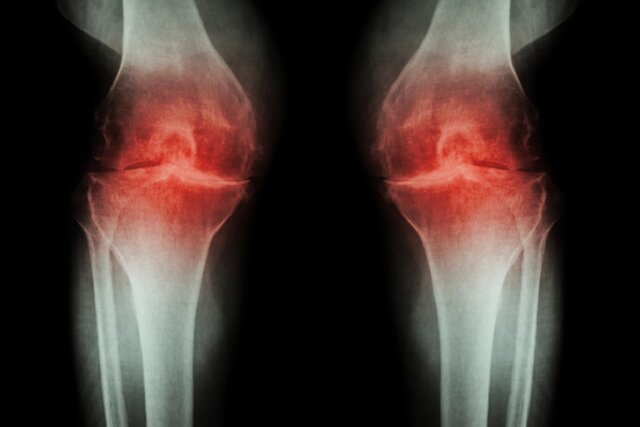

پژوهشگران آمریکایی در بررسی جدید خود توانستند مسیری را کشف کنند که دردهای ناشی از آرتروز را منتقل میکند و میتواند یک هدف درمانی جدید باشد.

به گزارش ایسنا و به نقل از نیو اطلس، آرتروز میتواند یک بیماری ناتوانکننده باشد و حرکات منظم را دردناک کند. پژوهشگران "دانشگاه ایالتی کارولینای شمالی"(NC State)، یک مسیر سیگنالدهی را شناسایی کردهاند که این درد را منتقل میکند. آنها با آزمایش روی موشها دریافتند که پس از مسدود شدن این مسیر، استفاده طبیعی از اندام بازگشته است. این کار میتواند به ارائه درمانهای جدید برای بیماران مبتلا به آرتروز کمک کند.